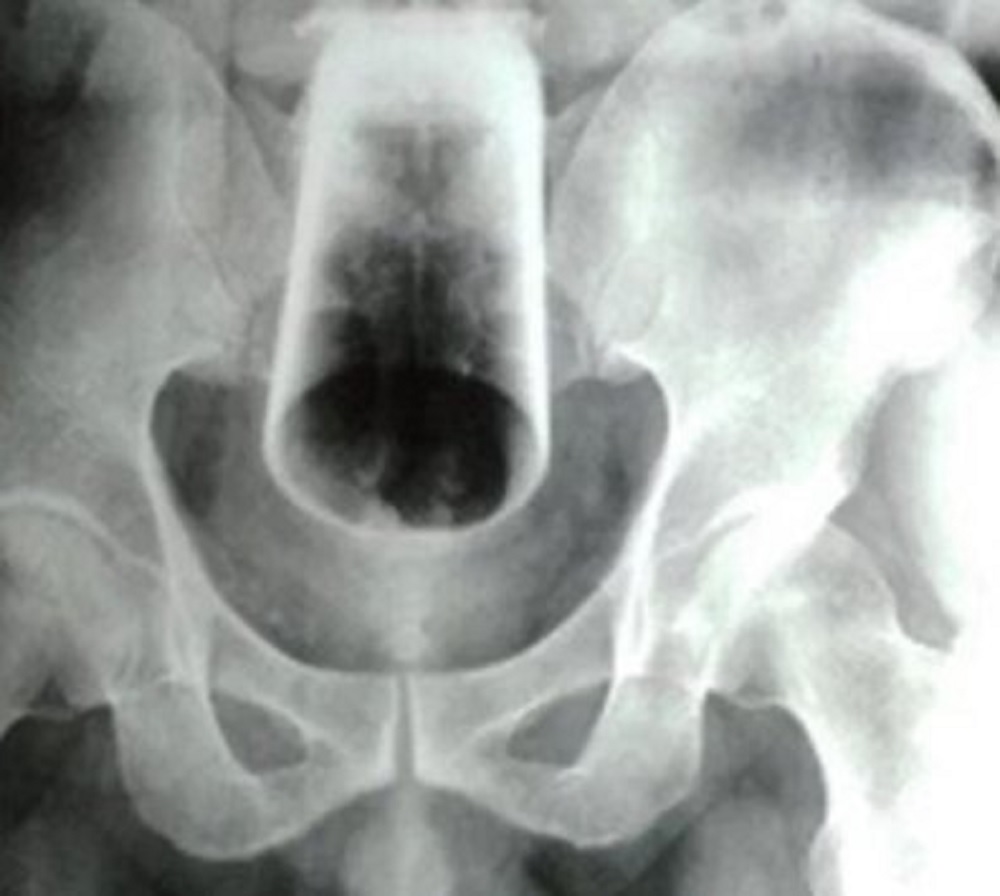

A vítima foi hospitalizada em Cáceres após um incidente inusitado. Segundo relatos, o homem inseriu o objeto na região anal, e, infelizmente, o copo se quebrou.

Diante da complexidade do caso, o paciente foi transferido para o Hospital Regional de Cáceres e está aguardando uma cirurgia.